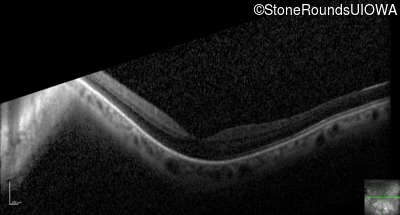

Optical Coherence Tomography - Right - 20/40 +2

Exemplar / OCT Stack

OCT Stack